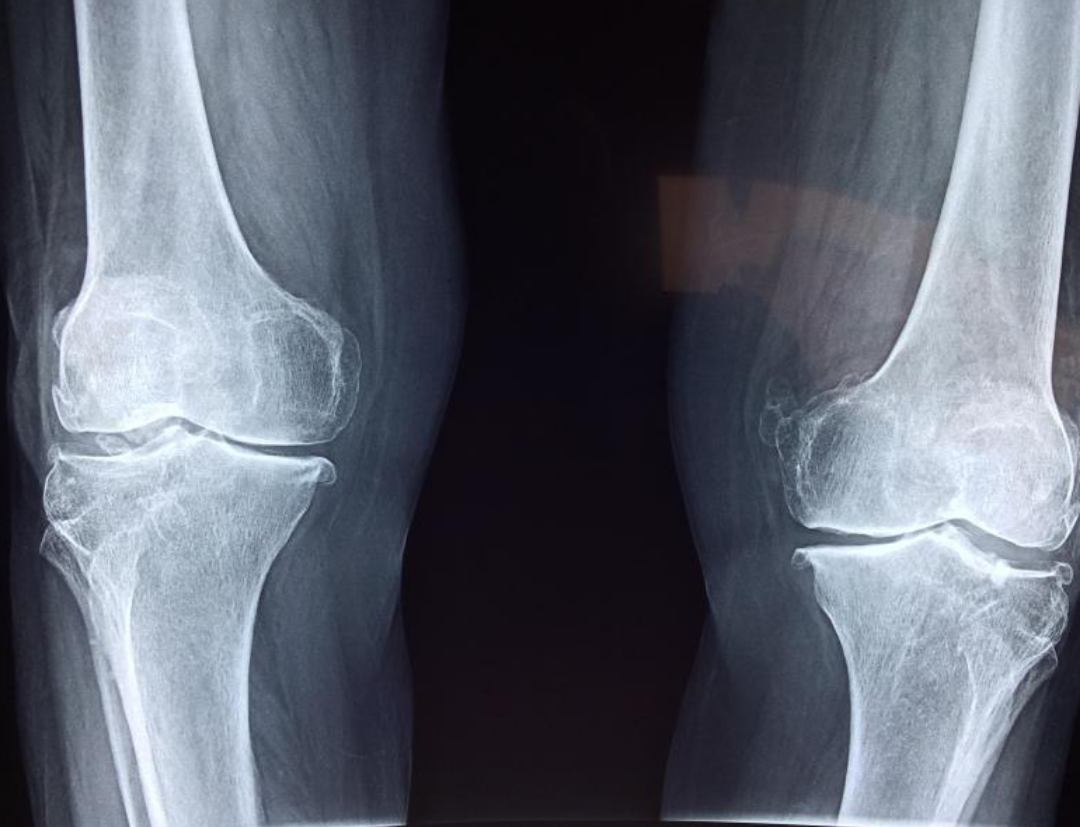

2. 관절 건강

보스웰리아는 관절 및 연골의 기능을 보호하는 역할을 하기도 합니다. 일부 연구 결과에서 보스웰리아를 섭취한 관절염 환자들에게서 관절 콩증 감소, 관절 운동 개선, 붓기 감소 등의 효과가 나타났다고 합니다.